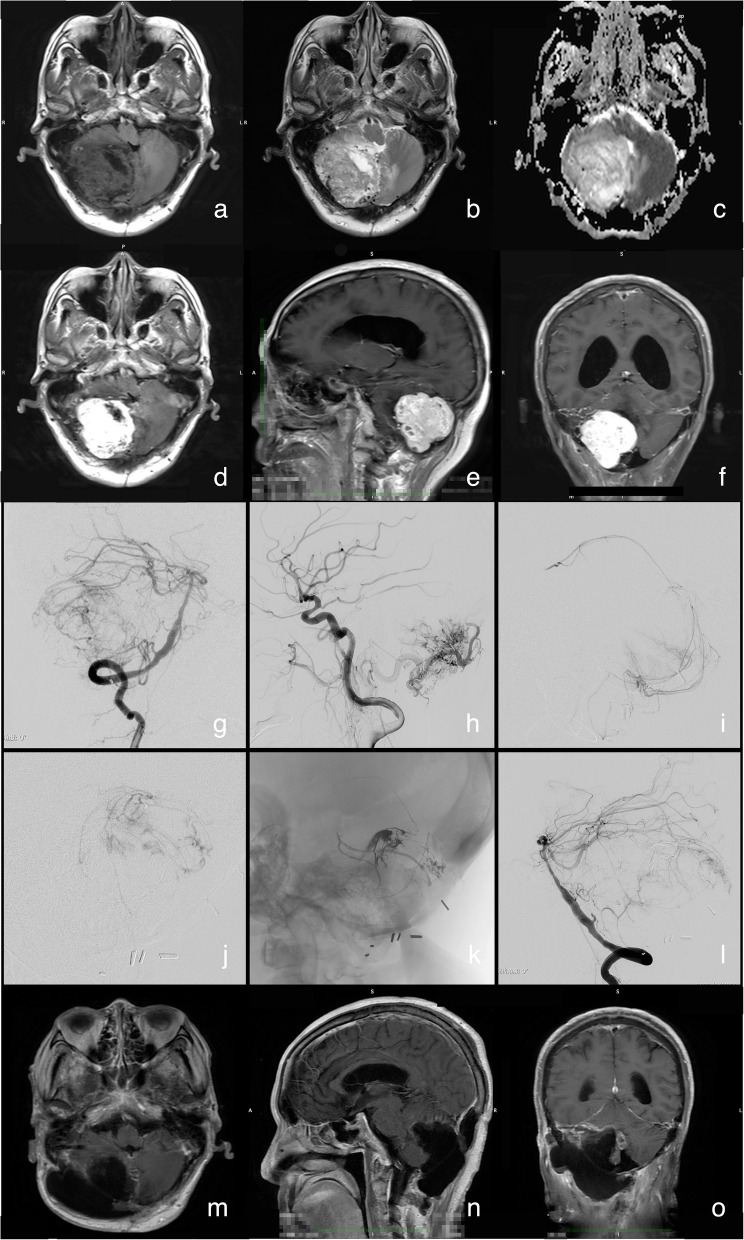

Results: In total, 31 hypervascular central nervous system tumor patients were recruited. The main pathological types included various types of meningiomas (45.2%), hemangioblastomas (16.1%), paragangliomas (9.7%), and solitary fibrous tumors (9.7%). Embolization of tumor-feeding arterial pedicles alone was achieved in 25 patients, and various materials, such as ethylene-vinyl alcohol copolymer, Guglielmi detachable coil, and silk suture segments, were used, in which the tumor blood supply was blocked satisfactorily and the texture became softer postembolization. Intratumoral vascular beds were embolized in six patients. The mean occlusion rate of the target pedicle was 83.3%. Gross-total resection was achieved in 22 patients (71.0%), with a mean blood loss volume of 1127 ± 1114.4 mL (ranging from 150 - 4500 ml). No embolization-related complications occurred. Deterioration of neurological deficits was observed in three patients (9.7%) at discharge.